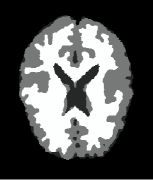

Example 3: real-world images. Test our method in two real-world images, i.e., camera man and MRI (magnetic resonance imaging) brain image which comes from medical imaging subject, see Fig. 4. We first test our method in noisy images and images with information lost. In Fig. 4, the variance used for adding noise is 0.01, and the percentage of information lost is . The conclusions we get are very close to those obtained when we test the methods in synthetic images in examples 1 and 2. From the rows one and three of Fig. 4, we see that all the methods give very good results in segmenting the two original real-world images. But for the images with information lost especially for the image in Fig. 4(A4), the results of methods [43, 23] are worse than the results of methods [6] and ours, see Fig. 4(B4), (C4), (D4), and (E4). Moreover, for the results of methods [6] and ours, we see that our result gives much more details for the white matter, see Fig. 4(D4) and (E4).

| (A4) | (B4) [43] (68.27) | (C4) [23] (74.28) | (D4) [6] (86.11) | (E4) Our (95.66) |